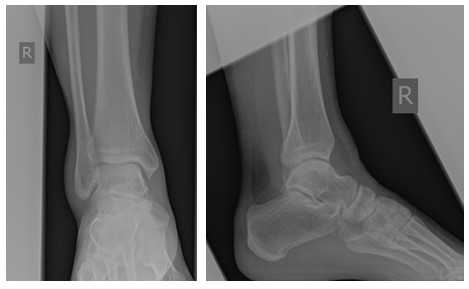

При детальном изучении снимков определяется увеличение межберцовой щели до 7,5 мм, уменьшения зоны перекрытия большеберцовой и малоберцовой костей до 5 мм, отсутствие на стороне поражения перекрытия тени таранной кости и малоберцовой кости.

На рентгенограмме костей правого и левого голеностопных суставов в прямой проекциии, снимки стоя - справа определяются признаки повреждения дистального межберцового синдесмоза - степень взаимного перекрытия берцовых костей 5мм (в норме больше 6мм) увеличенное большеберцовое - малоберцовое пространство - 7.5мм (в норме до 6мм).

При выполнении стресс рентгенограмм определяется выраженная латеральная нестабильность голеностопного сустава.